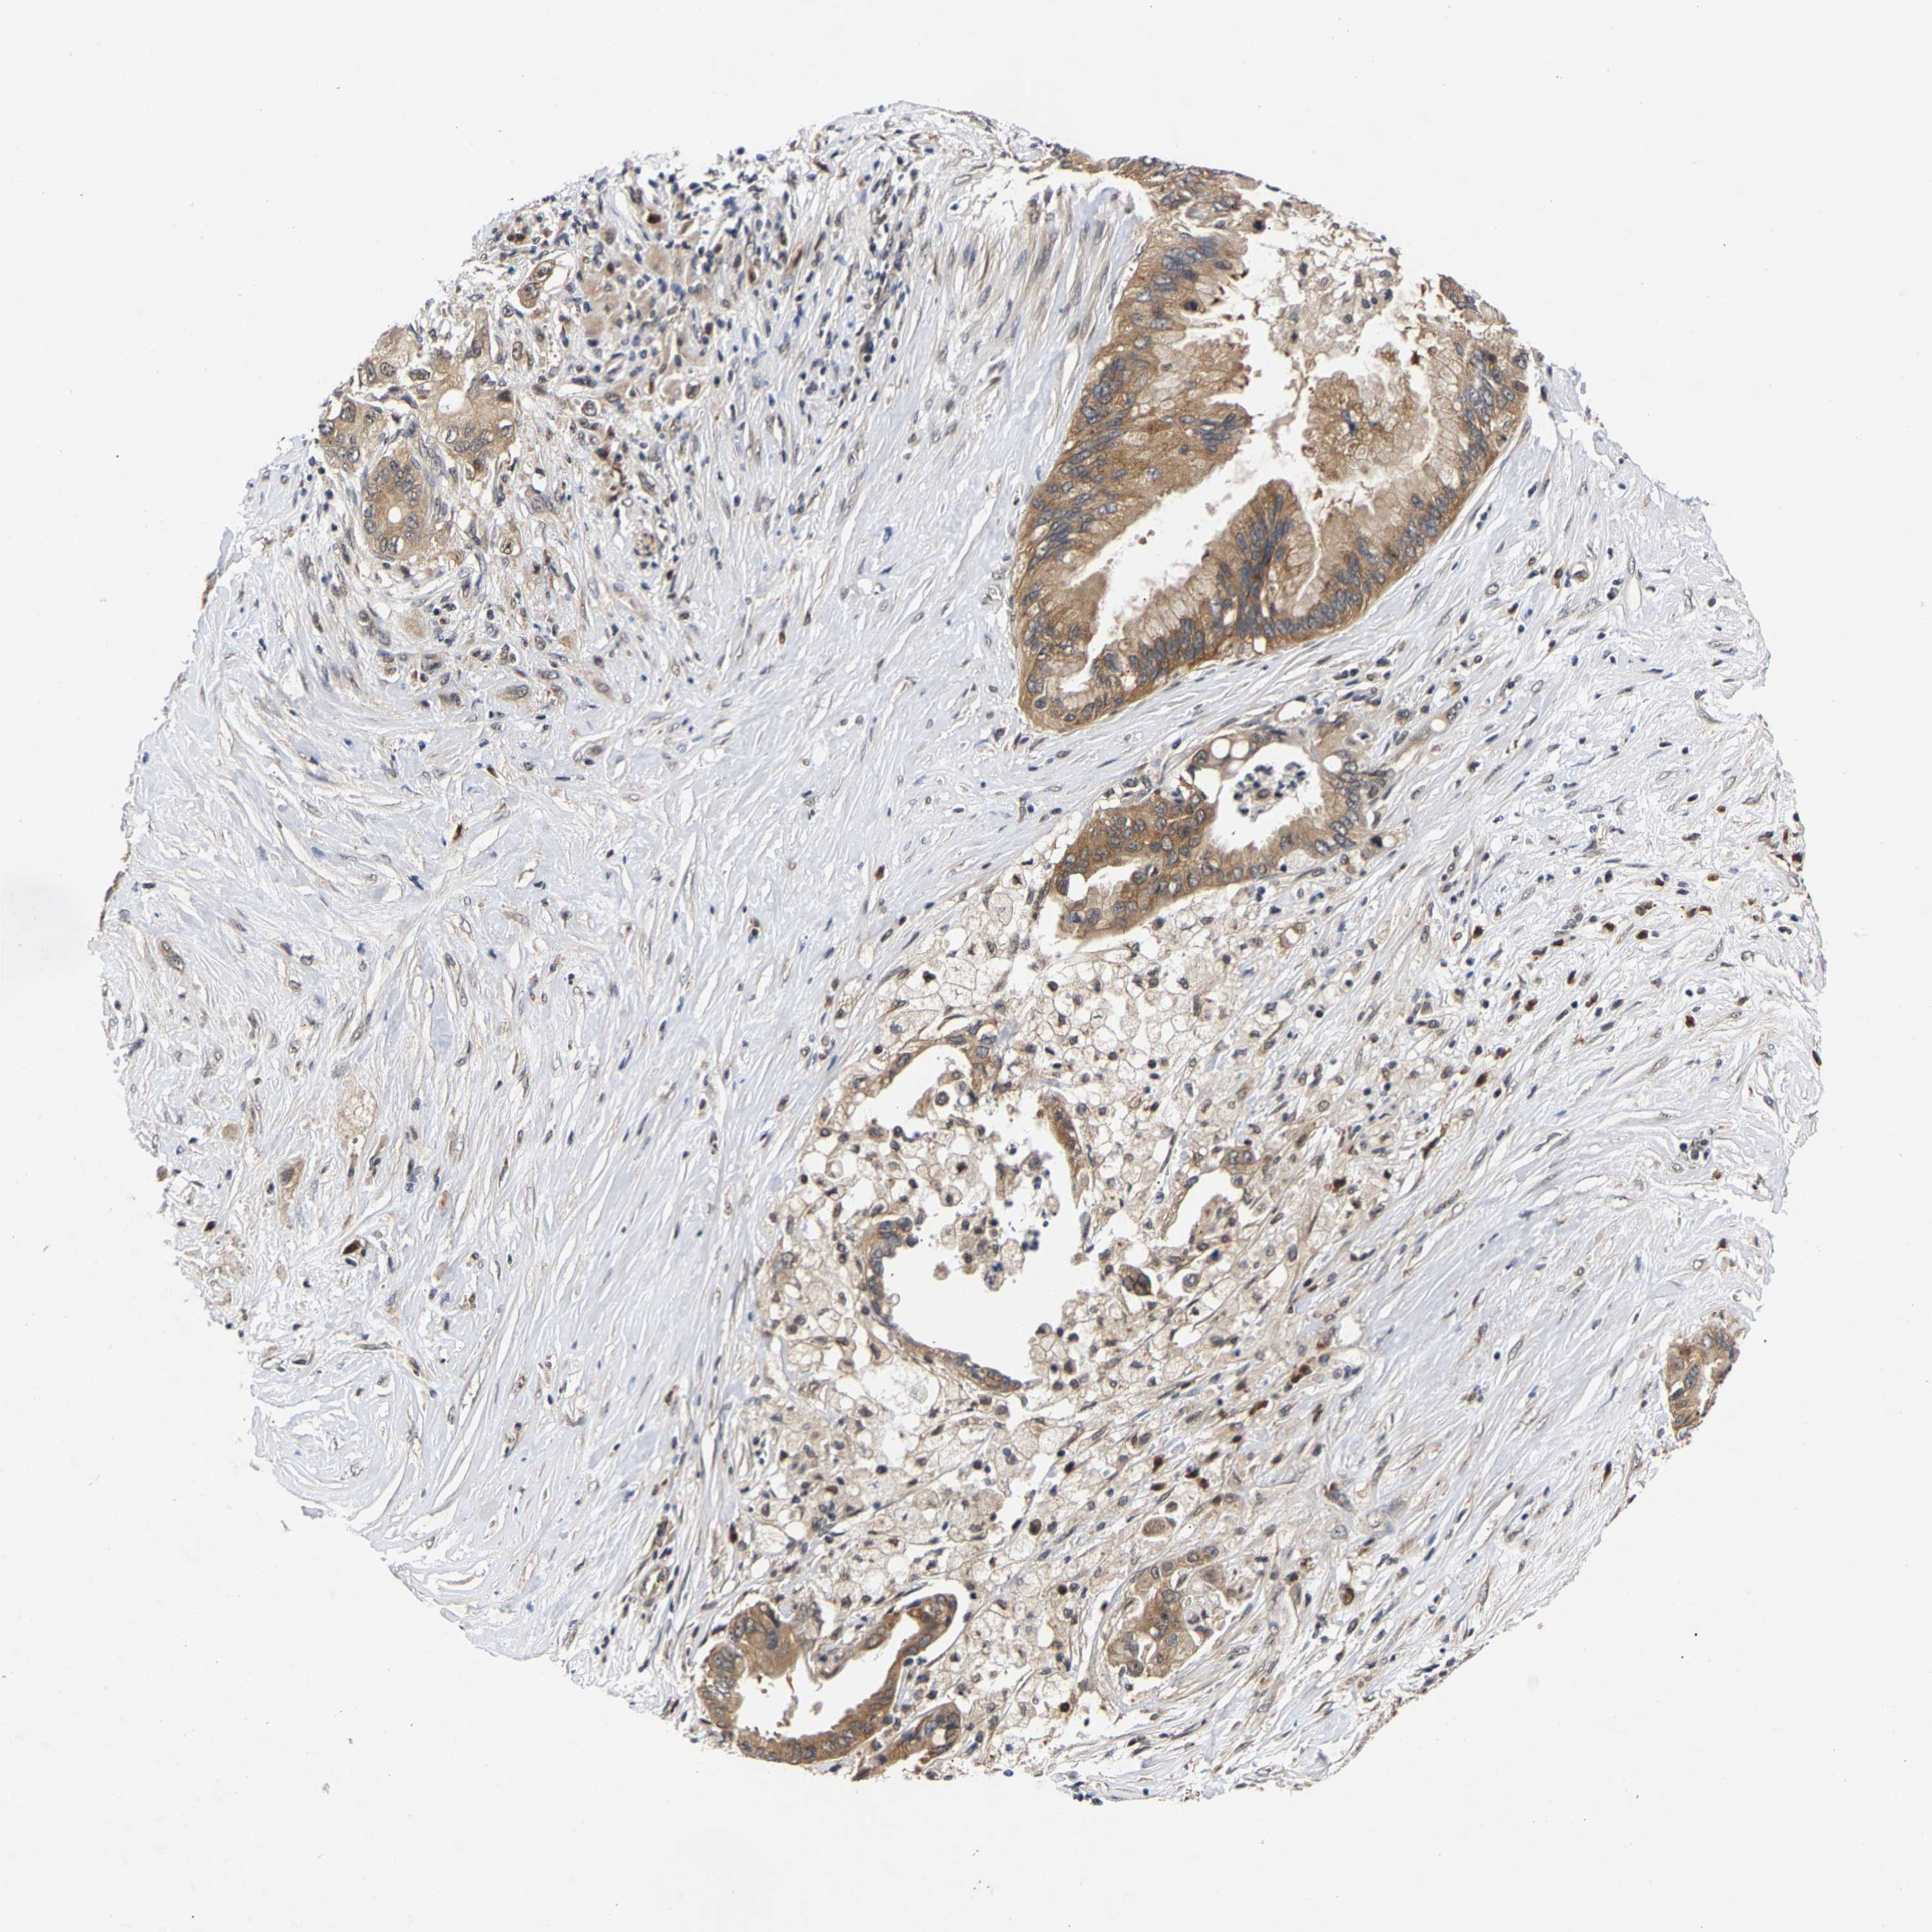

PANCREATIC CANCER - Protein expressioni

A mouse-over function shows sample information and annotation data. Click on an image to view it in a full screen mode. Samples can be filtered based on level of antibody staining by selecting one or several of the following categories: high, medium, low and not detected. The assay and annotation is described here.

Note that samples used for immunohistochemistry by the Human Protein Atlas do not correspond to samples in the TCGA dataset.

Antibody stainingi

Antibody staining in the annotated cell types in the current human tissue is reported as not detected, low, medium, or high, based on conventional immunohistochemistry profiling in selected tissues. This score is based on the combination of the staining intensity and fraction of stained cells.

Each image is clickable and will lead to virtual microscopy that enables deeper exploration of all samples and also displays staining intensity scores, fraction scores and subcellular localization as well as patient and tissue information for each sample.

Antibody HPA020430

Antibody CAB020767

Staining

High

Medium

Low

Not detected

Intensity

Strong

Moderate

Weak

Negative

Quantity

>75%

75%-25%

<25%

None

Location

Nuclear

Cytoplasmic/membranous

Cytoplasmic/membranous,nuclear

Adenocarcinoma, NOS